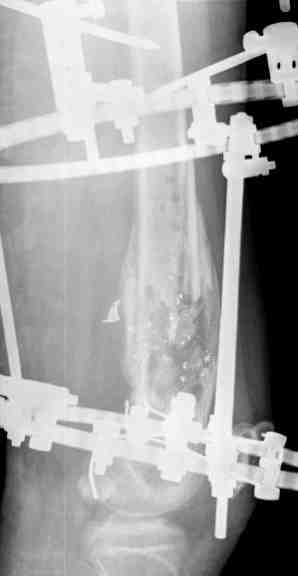

Выше представлены рентгенограммы открытого оскольчатого перелома нижней трети голени X-rays of Compound Comminuted # Distal/3 Lt Tibia

Операционные снимки перед и после наложения аппарата Илизарова In operation room before and after Ilizarov apparatus has been applied

Послеоперационные рентгенограммы Postoperative X-rays

В нижнем ряду представлены рентгенограммы после окончательной репозиции. And final reduction after Hexapod program has been finished